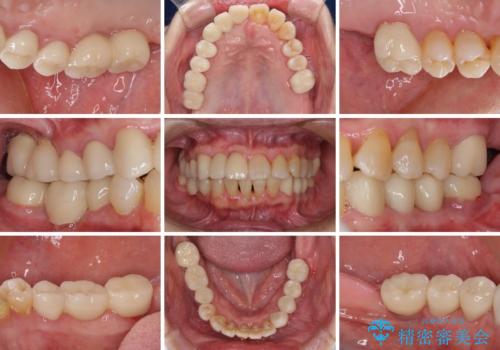

下顎2前歯の欠損 インビザラインによる抜歯矯正

- 下顎前歯欠損による歯列不正を気にして来院された患者様です。

下顎の歯列が小さく、下顎前歯が隠れてしまう過蓋咬合(ディープバイト)であったため、

①下顎歯列を拡大し、欠損部に2歯分のインプラント補綴をおこなう

②上顎左右第一小臼歯2本を抜歯、下顎歯列を拡大し、欠損部に1歯分のインプラント補綴をおこなう

③上顎左右第一小臼歯2本を抜歯し、下顎はスペースを閉じる

のいずれかを提案しました。(①から③の順番にお勧めのプランとなります)

いずれもワイヤー矯正が望ましい治療方法ですが、家が遠方であり、近い将来出産される予定もあるとのことで、何とかマウスピース矯正でも対応可能な③にて治療を行うこととしました。

マウスピースでの抜歯矯正特有の抜歯スペースに向かって奥歯が傾斜する動きが顕著に表れ、ディープバイトは改善されませんでした。

前歯のみが強く接触し、奥歯で咬めない期間も続いたため、ワイヤー装置などを補助的に使用し、何とか終了させることができました。